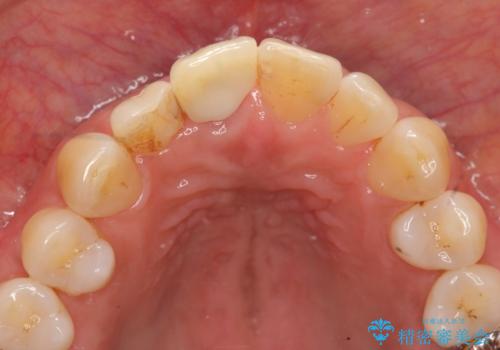

- 前歯を外傷により失い、審美性の改善を求めて来院されました。

横の歯を削る必要のあるブリッジ治療、着脱の必要な入れ歯に強い抵抗があったためインプラント治療を計画します。

前歯のインプラントを審美的に仕上げるには、インプラント周囲に十分な骨の量と厚みのある歯肉、そして埋入位置の精密な位置付けが重要です。